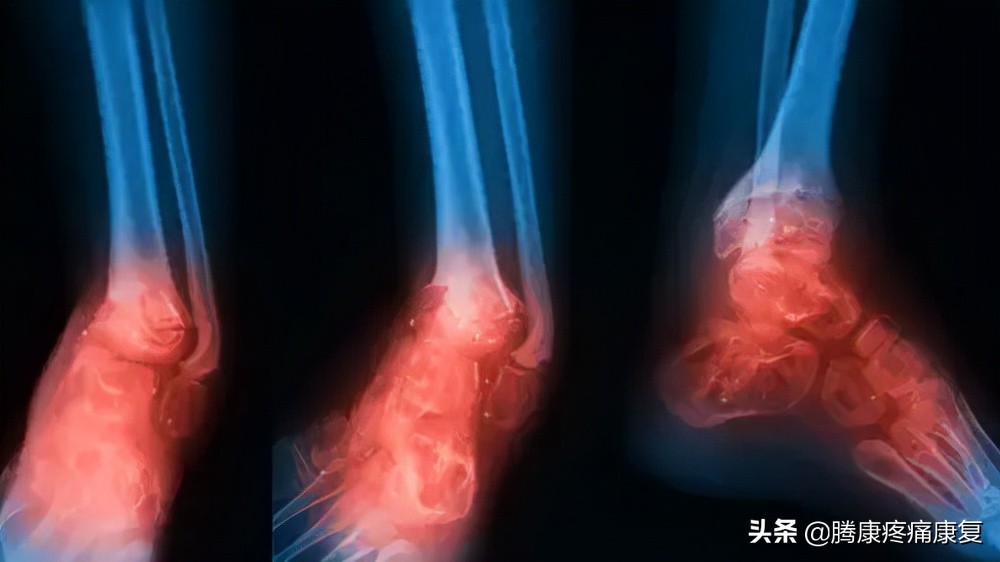

跟腱炎或断裂

跟腱是人体最大的肌腱,它位于腿部后侧,连接小腿肌肉和脚跟骨。

当肌腱受到刺激时,通常是由于过度使用,可能会感觉到腿后部的灼痛,通常就在脚跟上方。也可能有小腿疼痛和僵硬感,这就是众所周知的跟腱炎。

当跟腱肌腱撕裂时,腿后部可能会突然出现剧烈疼痛。腿可能很难承受任何重量。有些人在受伤时还会听到“砰”的一声。